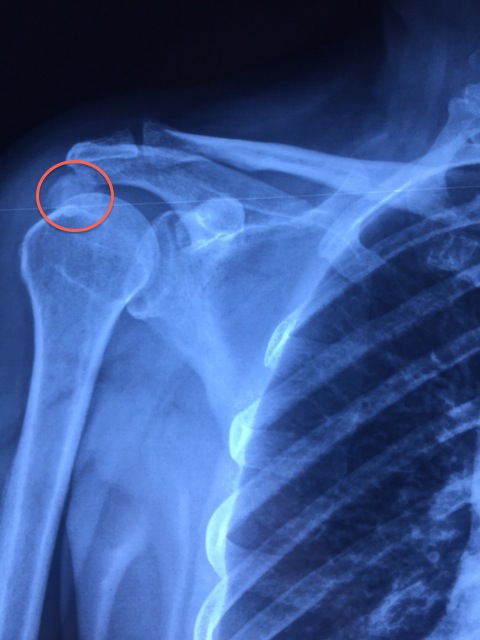

Bệnh Lắng Đọng Tinh Thể Hydrixyapatile (HADD)

Có thể khi đi khám về khớp hoặc tình cờ chụp phim X quang, bạn nhận thấy có 1 đám cản quang ở quanh khớp của mình, đó cũng có thể là bạn bị bệnh lắng đọng tinh thể Hydroxyapatite ở các điểm bám của gân vùng gần khớp, đặc biệt hay gặp ở khớp […]